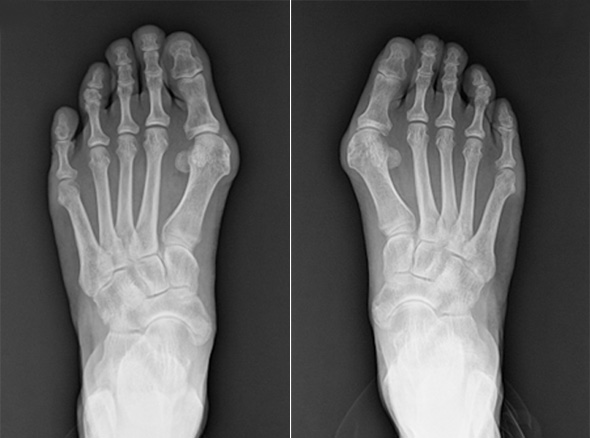

MICA, minimally invasive Chevron & Akin osteotomy

이전에는 무지외반 수술은 5cm 이상 피부를 절개하고 뼈를 싸고 있는 골막을 절개하여 수술을 하였습니다.

그래서 무지외반 수술은 통증이 심한 수술에 속하였지만

비절개 무지외반 교정술을 시행하고 나서는 획기적으로 회복 속도가 빨라졌고,

골막을 절개하지 않기 때문에 수술 후 통증도 많이 줄었습니다.

비절개 무지외반 교정술은 나사와 절골침이 들어갈 정도의 작은 구멍만 내고 하는 수술로 흉터는 낫고 나서는

거의 점처럼 보입니다. 수술 다음 날부터 큰 통증 없이 딛고 걸어 다니는 것도 가능합니다.